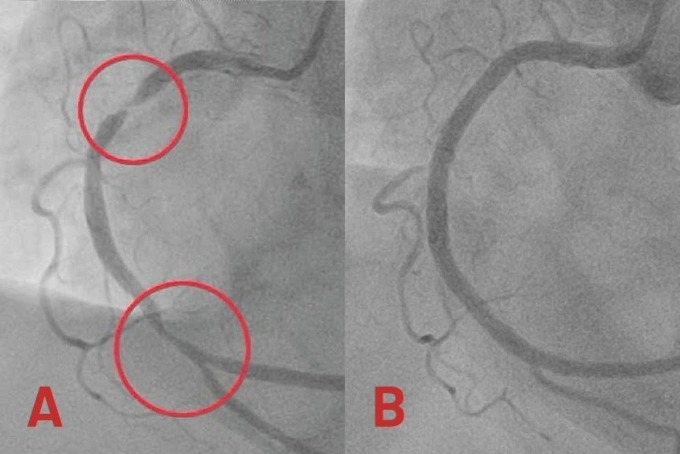

Mạch vành phải hẹp nặng nhiều chỗ (hình A) và sau khi được can thiệp tái thông (hình B). Ảnh: Bệnh viện Tâm Anh

Động mạch vành phải người bệnh bị hẹp khít đến 99% đoạn giữa và hẹp 80-90% đoạn xa. Êkíp luồn dây dẫn từ động mạch quay (ở cổ tay) đi qua vị trí hẹp nghẽn nặng để nong rộng mạch máu, mở đường cho việc đưa stent vào tái thông mạch vành. Sau gần một giờ, bác sĩ đặt thành công hai stent phủ thuốc tại hai vị trí hẹp nặng, khơi thông con đường đưa máu từ động mạch vành phải đến nuôi tim.